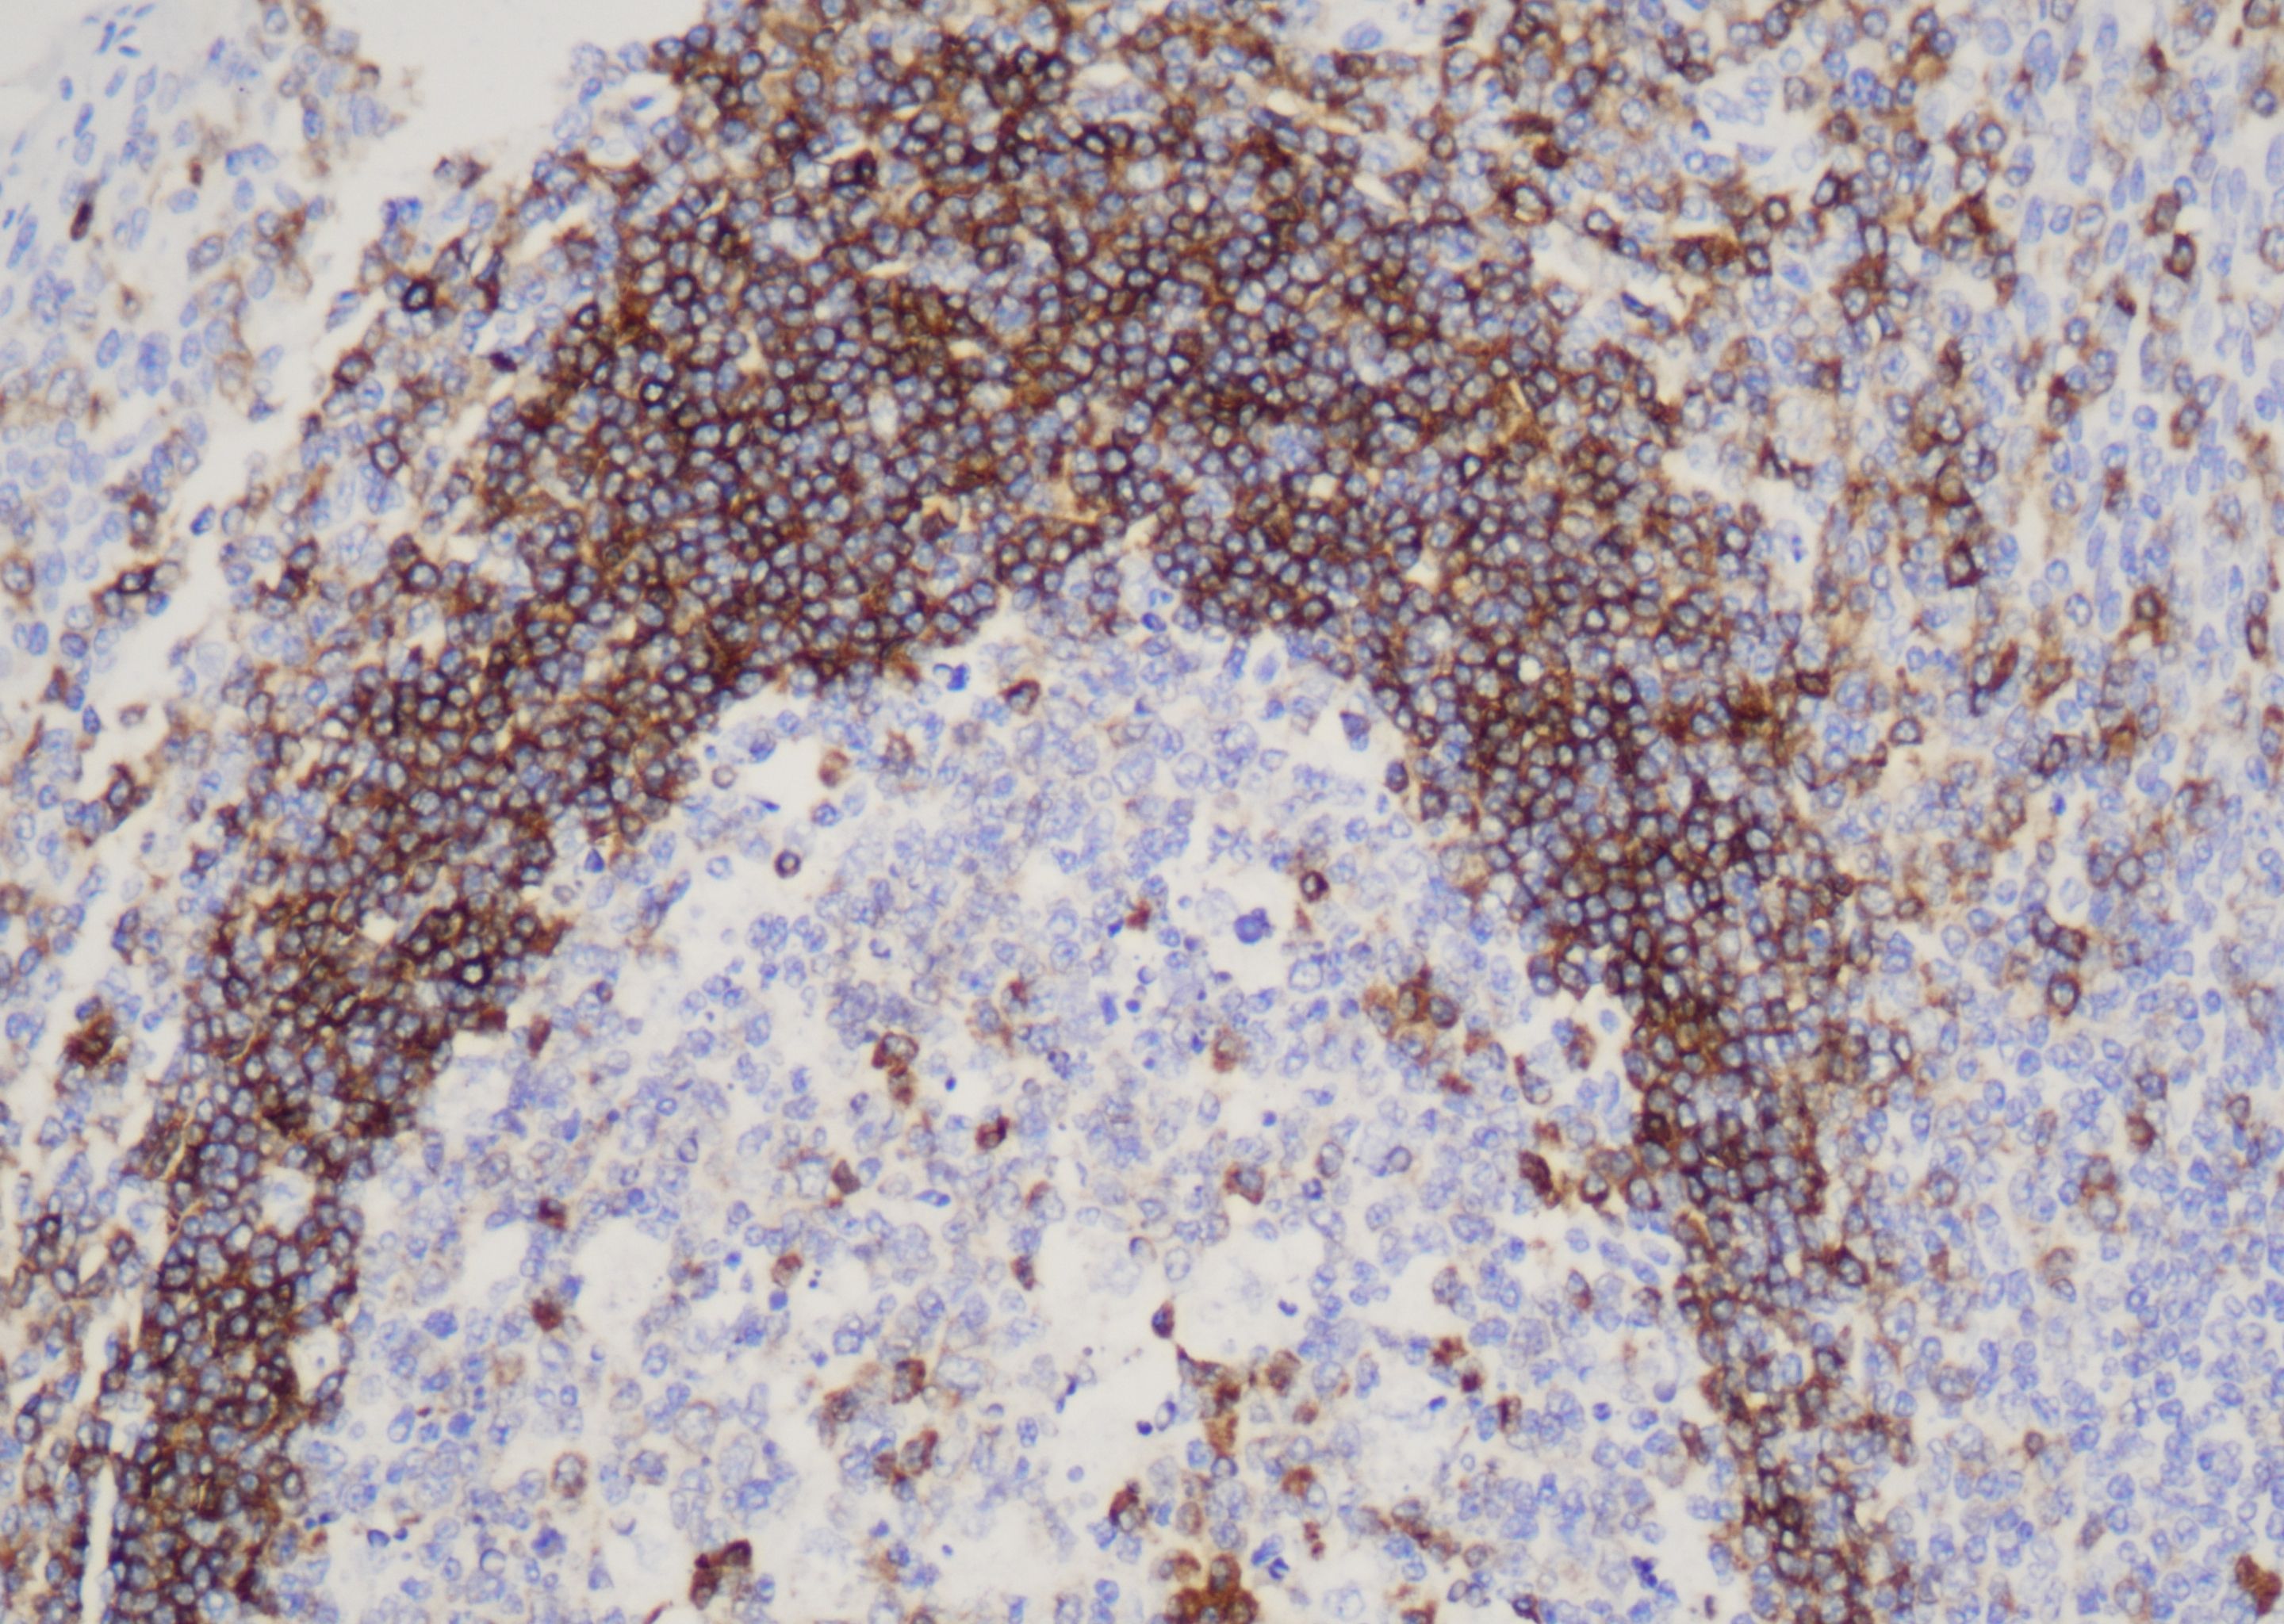

达科为提供200+种IHC一抗产品,有鼠源和兔源两类抗体,手工和仪器均可适配,一抗产品均为单克隆抗体,能够确保与目标抗原结合的特异性,同时一抗具有极高的灵敏度,可以在样本中检测到低表达水平的目标抗原,并获取可靠的结果。